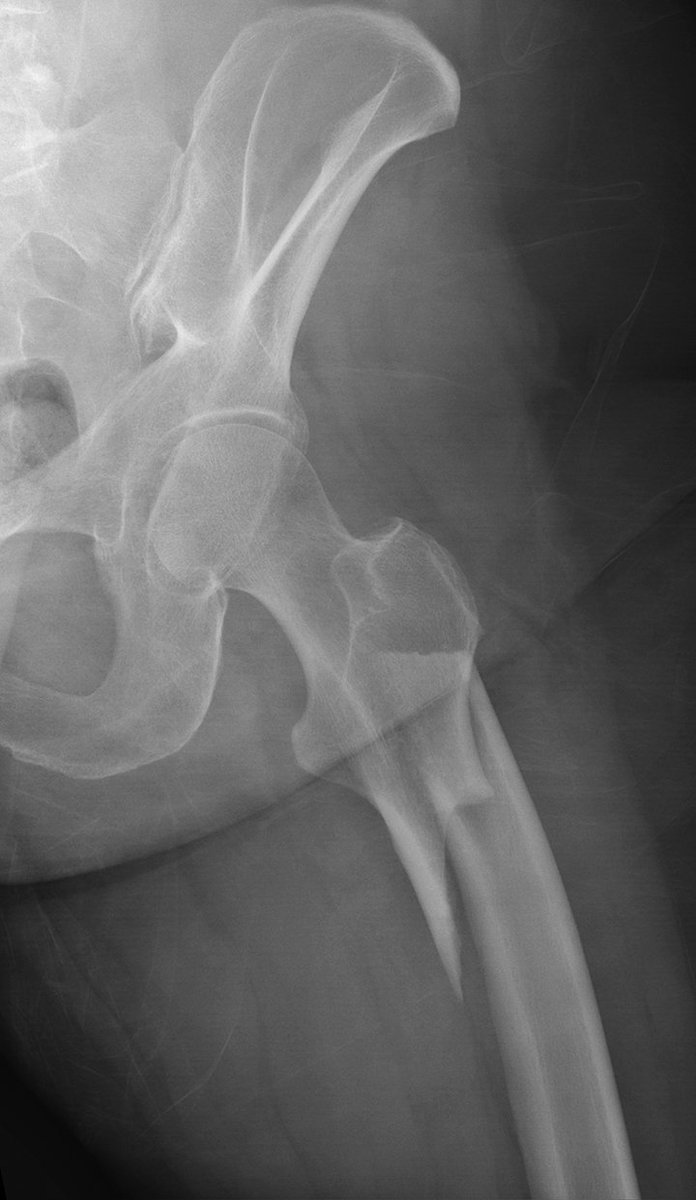

#CaseOfTheWeek...End🎉 📢✅Answer for Case #20: Bisphosphonate subtrochanteric fracture (atypical) Have a great week and happy June!!🥳🎉 #FOAMrad #RadEd #MedEd #OrthoEd #OrthoTwitter SSR_RWG UWisconsin Radiology Residents OTA Online

#CaseOfTheWeek...End🎉

📢✅Answer for Case #20: Bisphosphonate subtrochanteric fracture (atypical)